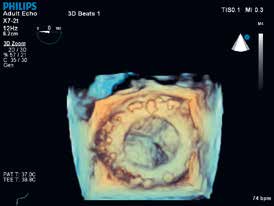

二尖瓣导航 (MVNA.I.)

二尖瓣导航(MVNA.I.)是旨在获得二尖瓣实时三维容积并通过八个引导下的步骤将其转化为易于解读的模型,提供二尖瓣测量和计算的全面列表。跟以往的工具相比,二尖瓣导航建模和测量减少了89%的点击次数。

二尖瓣导航 (MVNA.I.)在处理过程的每一部分中减少步骤:

• 瓣环数据的获取减少了74%的点击,同时在无用户交互的情况下提供了自动瓣叶描记。

• 二尖瓣导航(MVNA.I.)使用简单的指令和清晰的图形来引导整个处理过程,使之比以前的二尖瓣量化工具更容易使用。

• 二尖瓣导航(MVNA.I.)的结果完成时可在屏幕显示,加速访问所需数据的过程。

二尖瓣导航(MVNA.I.)获取二尖瓣的实时三维容积,并在短短的8个引导步骤下将之转化易于解读的模型。